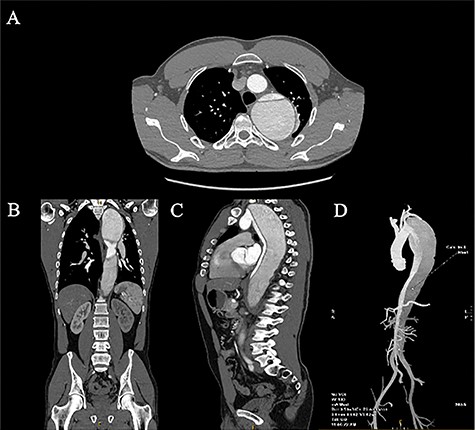

Three months later, the patient represented with severe left sided chest pain. A CT aortogram demonstrated fusiform dilatation of the distal arch and aorta measuring 73 × 69 mm (Fig. 1) with interval false lumen dilation. The decision was made to proceed with an open thoracoabdominal aortic aneurysm (TAAA) repair utilising cardiopulmonary bypass with deep hypothermic circulatory arrest. A pre-operative cerebrospinal drain was placed to decrease the risk of spinal ischaemia. The patient was positioned in left lateral position with a thoracoabdominal incision made through the fifth intercostal space. Retroperitoneal dissection revealed vessels of good calibre and an extensive TAAA (Fig. 2). Peripheral cardiopulmonary bypass was instituted via the left femoral artery and vein utilising an 8 mm Dacron graft, and a 25Fr venous cannula. The patient was cooled to 18 degrees Celsius and placed in Trendelenburg positioning for clamping of the mid-thoracic aorta.

April 2020 CT aortogram demonstrating a large 72.7 mm × 68.6 mm fusiform aneurysm: (A) axial slices, (B) coronal slices, (C) sagittal slices, and (D) 3D reconstruction.